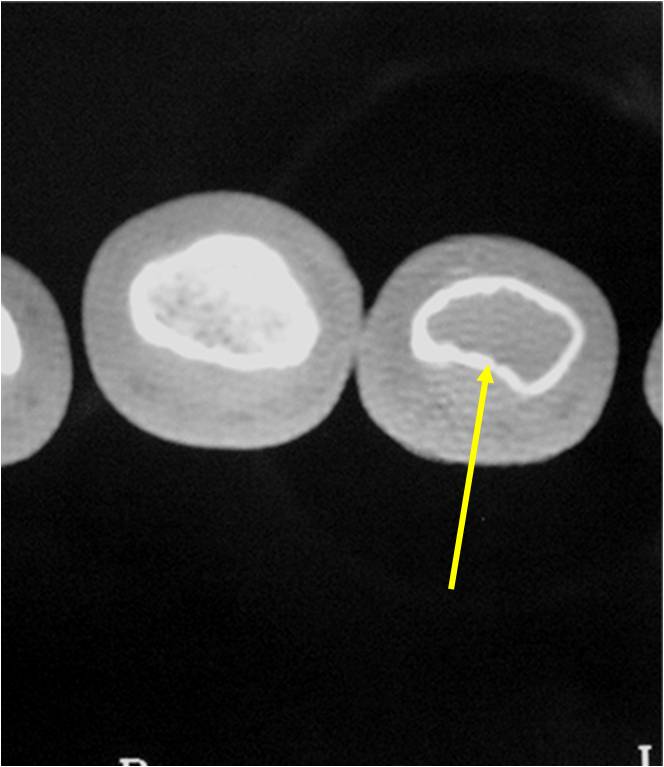

Geographic Lesion Bony Expansion Minimal Calcification Some Enchondromas do not calcify

- Endosteal erosion>2/3 cortical thickness on a CT scan